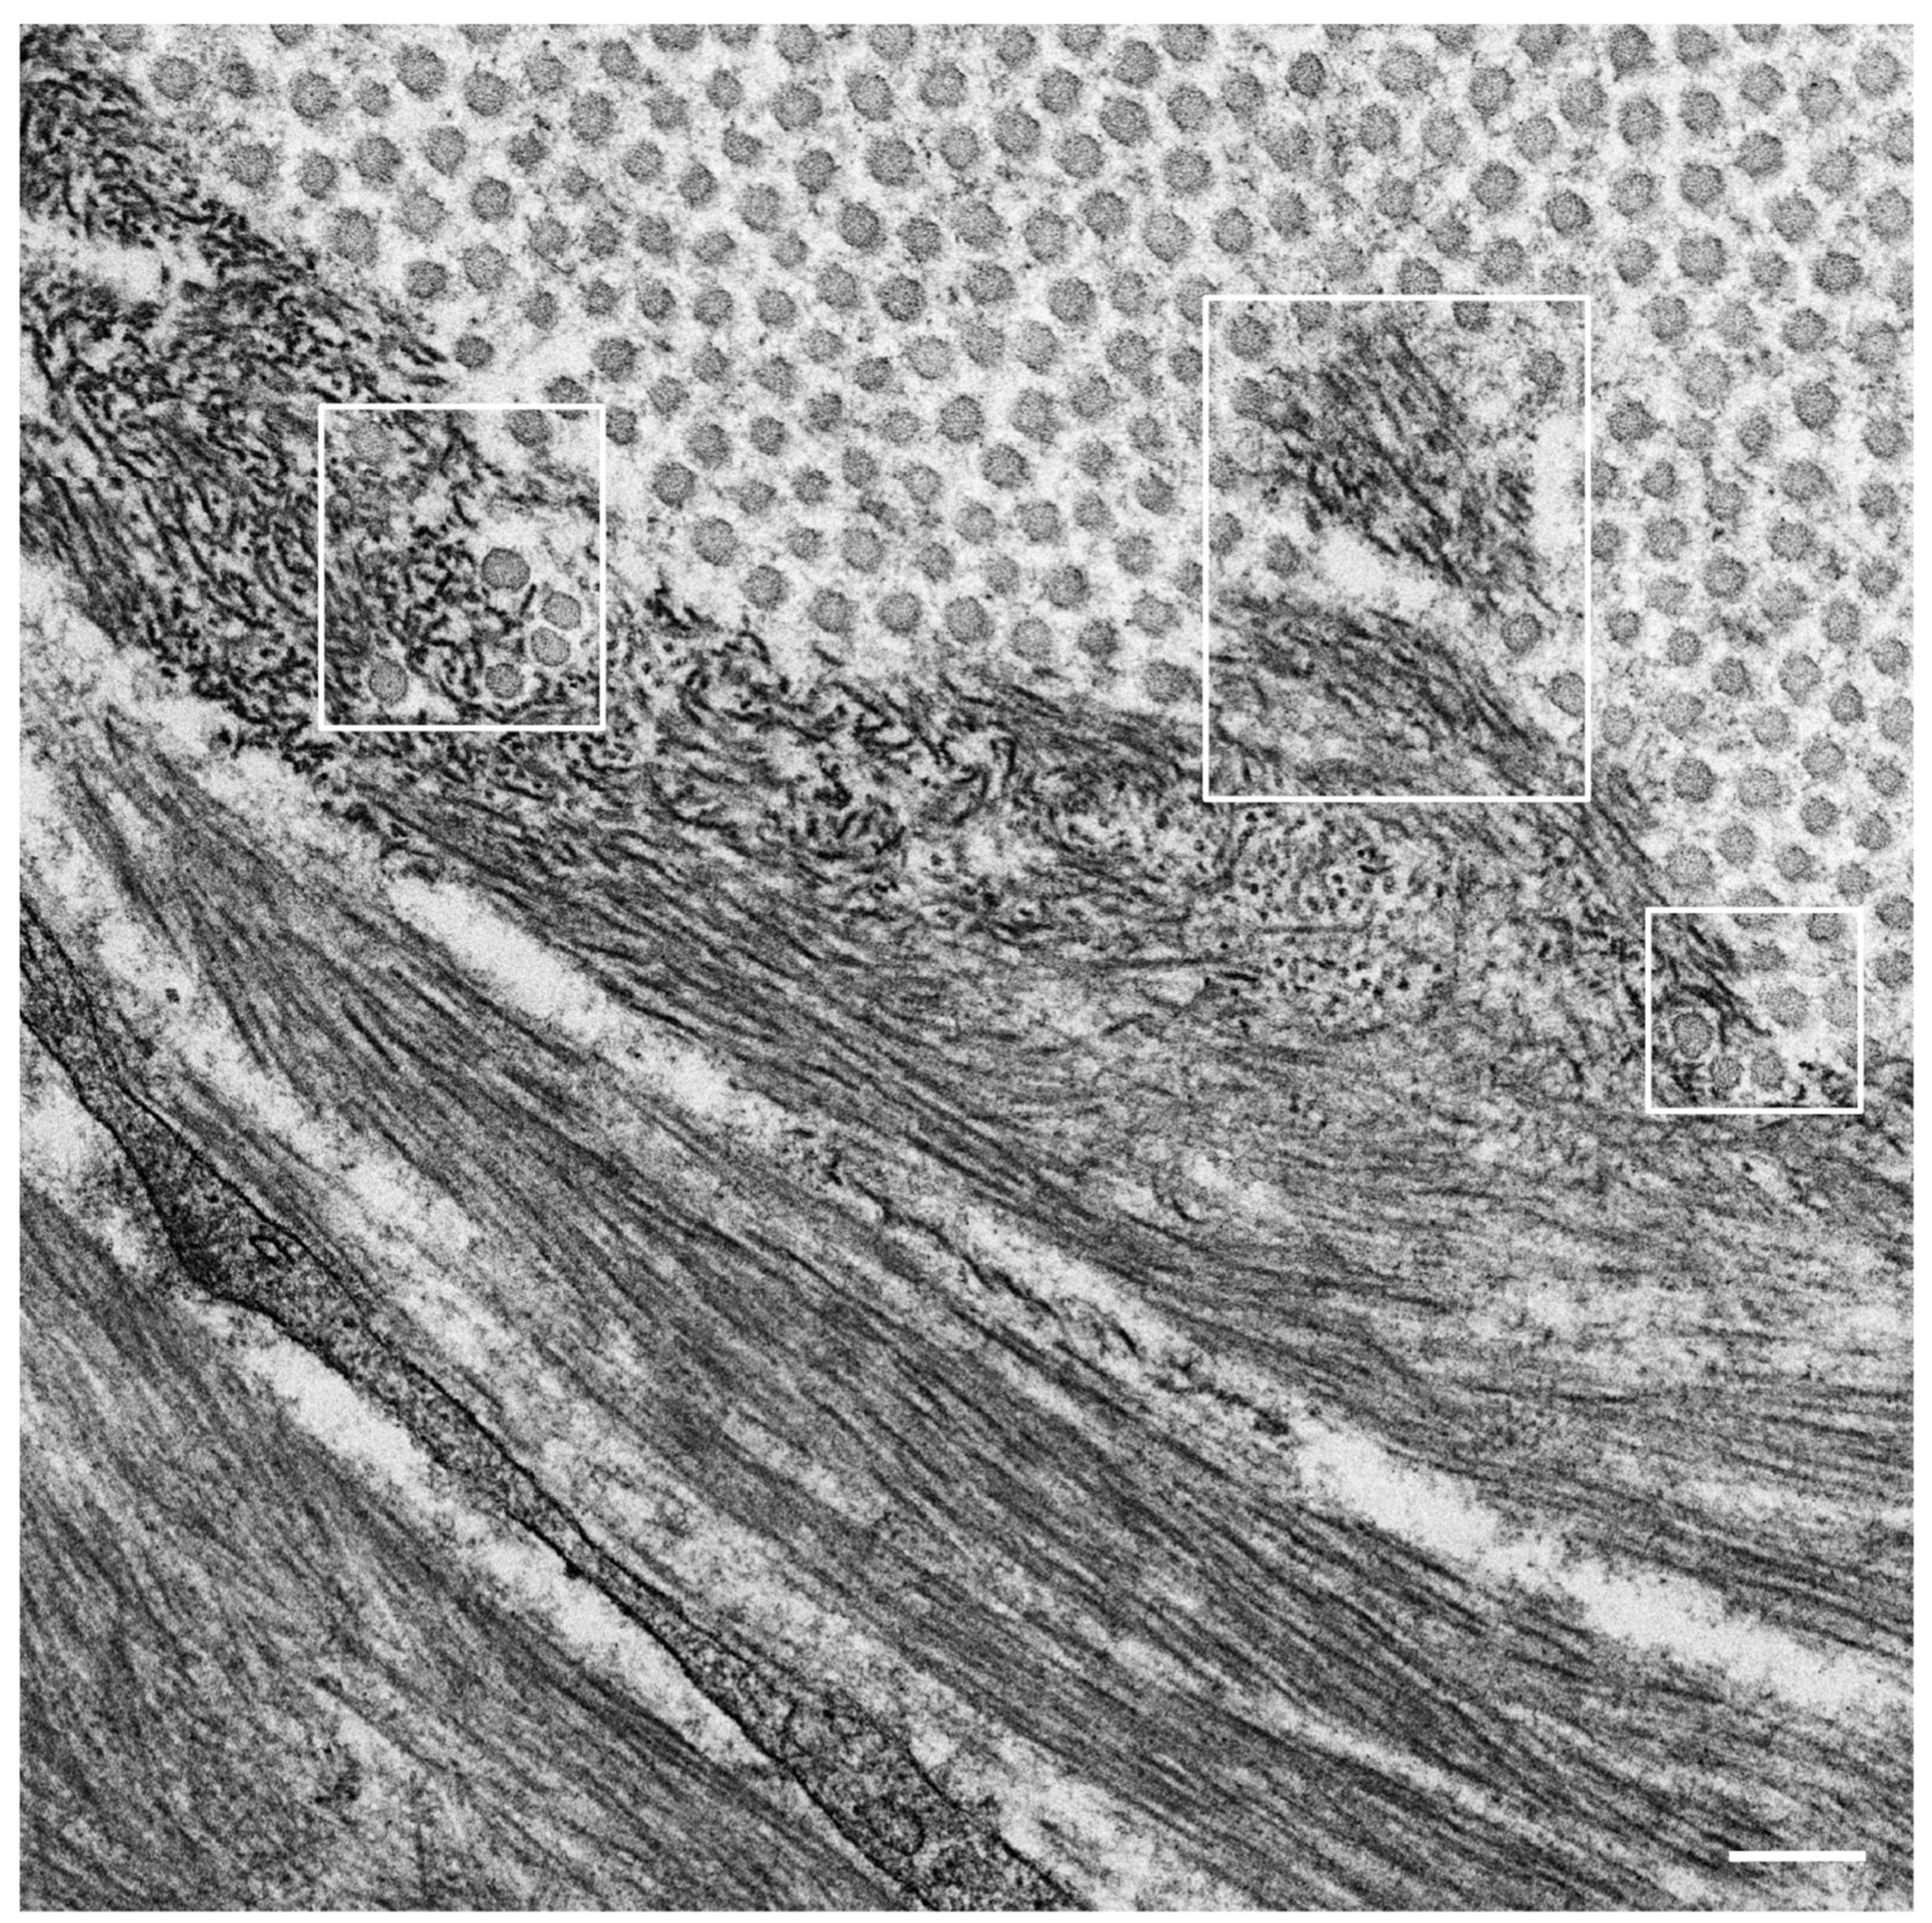

- Koike, H.; Nishi, R.; Ikeda, S.; Kawagashira, Y.; Iijima, M.; Sakurai, T.; Shimohata, T.; Katsuno, M.; Sobue, G. The morphology of amyloid fibrils and their impact on tissue damage in hereditary transthyretin amyloidosis: An ultrastructural study. J. Neurol. Sci. 2018, 394, 99–106. [Google Scholar] [CrossRef] [PubMed]